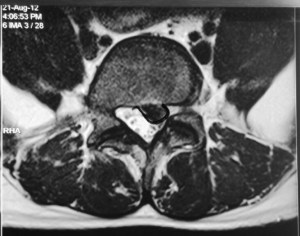

This is a patient who presented with sciatica in his left leg from a L5/S1 posterolateral left sided slipped disc in 2012.

He was offered surgery but chose conservative treatment.

His pain eventually resolved over a period of 3 to 6 months after taking medications and undergoing intensive physiotherapy.

The same patient underwent a new MRI scan of his lumbar spine in 2015 for lower backache. There was no sciatica in his lower limbs.

The MRI showed resorption of the previous large left sided slipped disc.